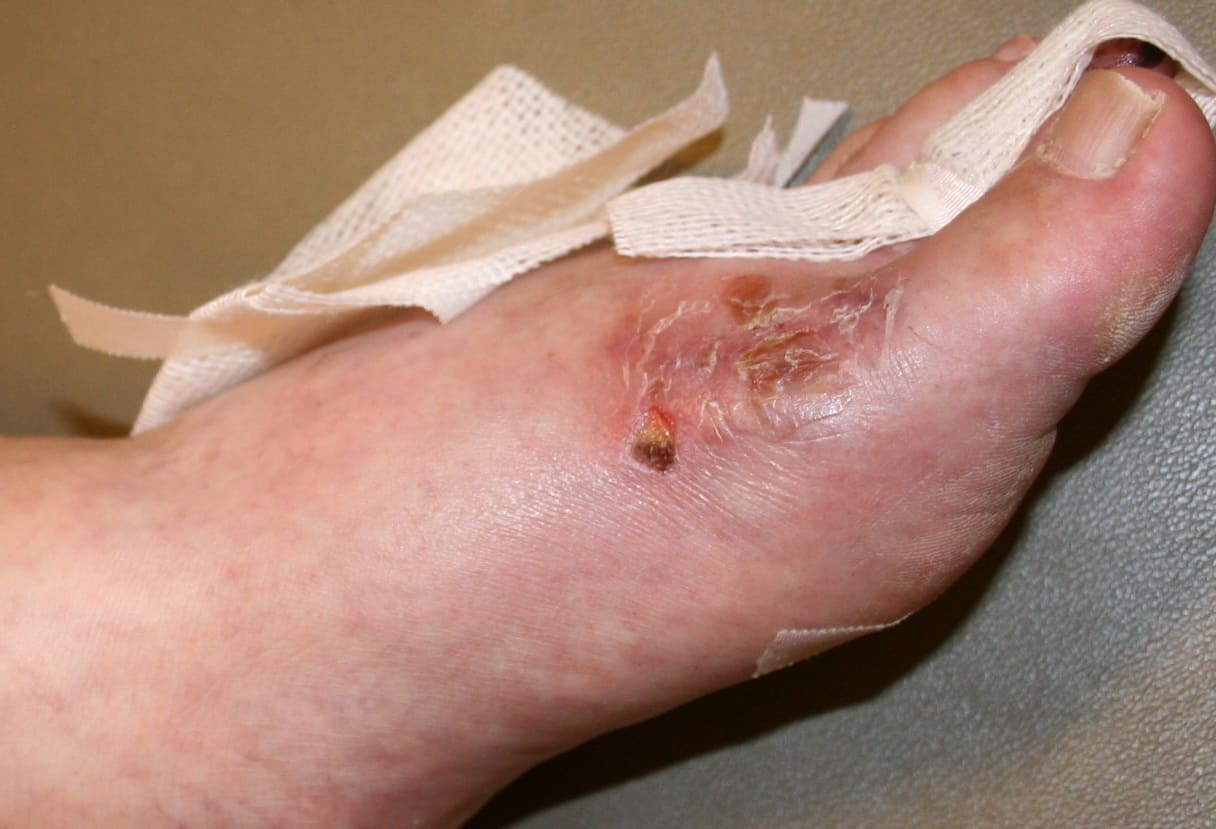

Pemphigis Vulgaris =الفقاع الشائع